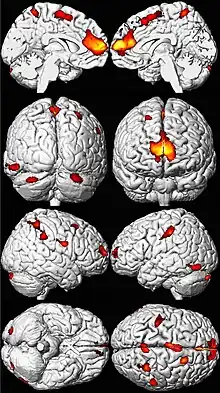

.png.webp)